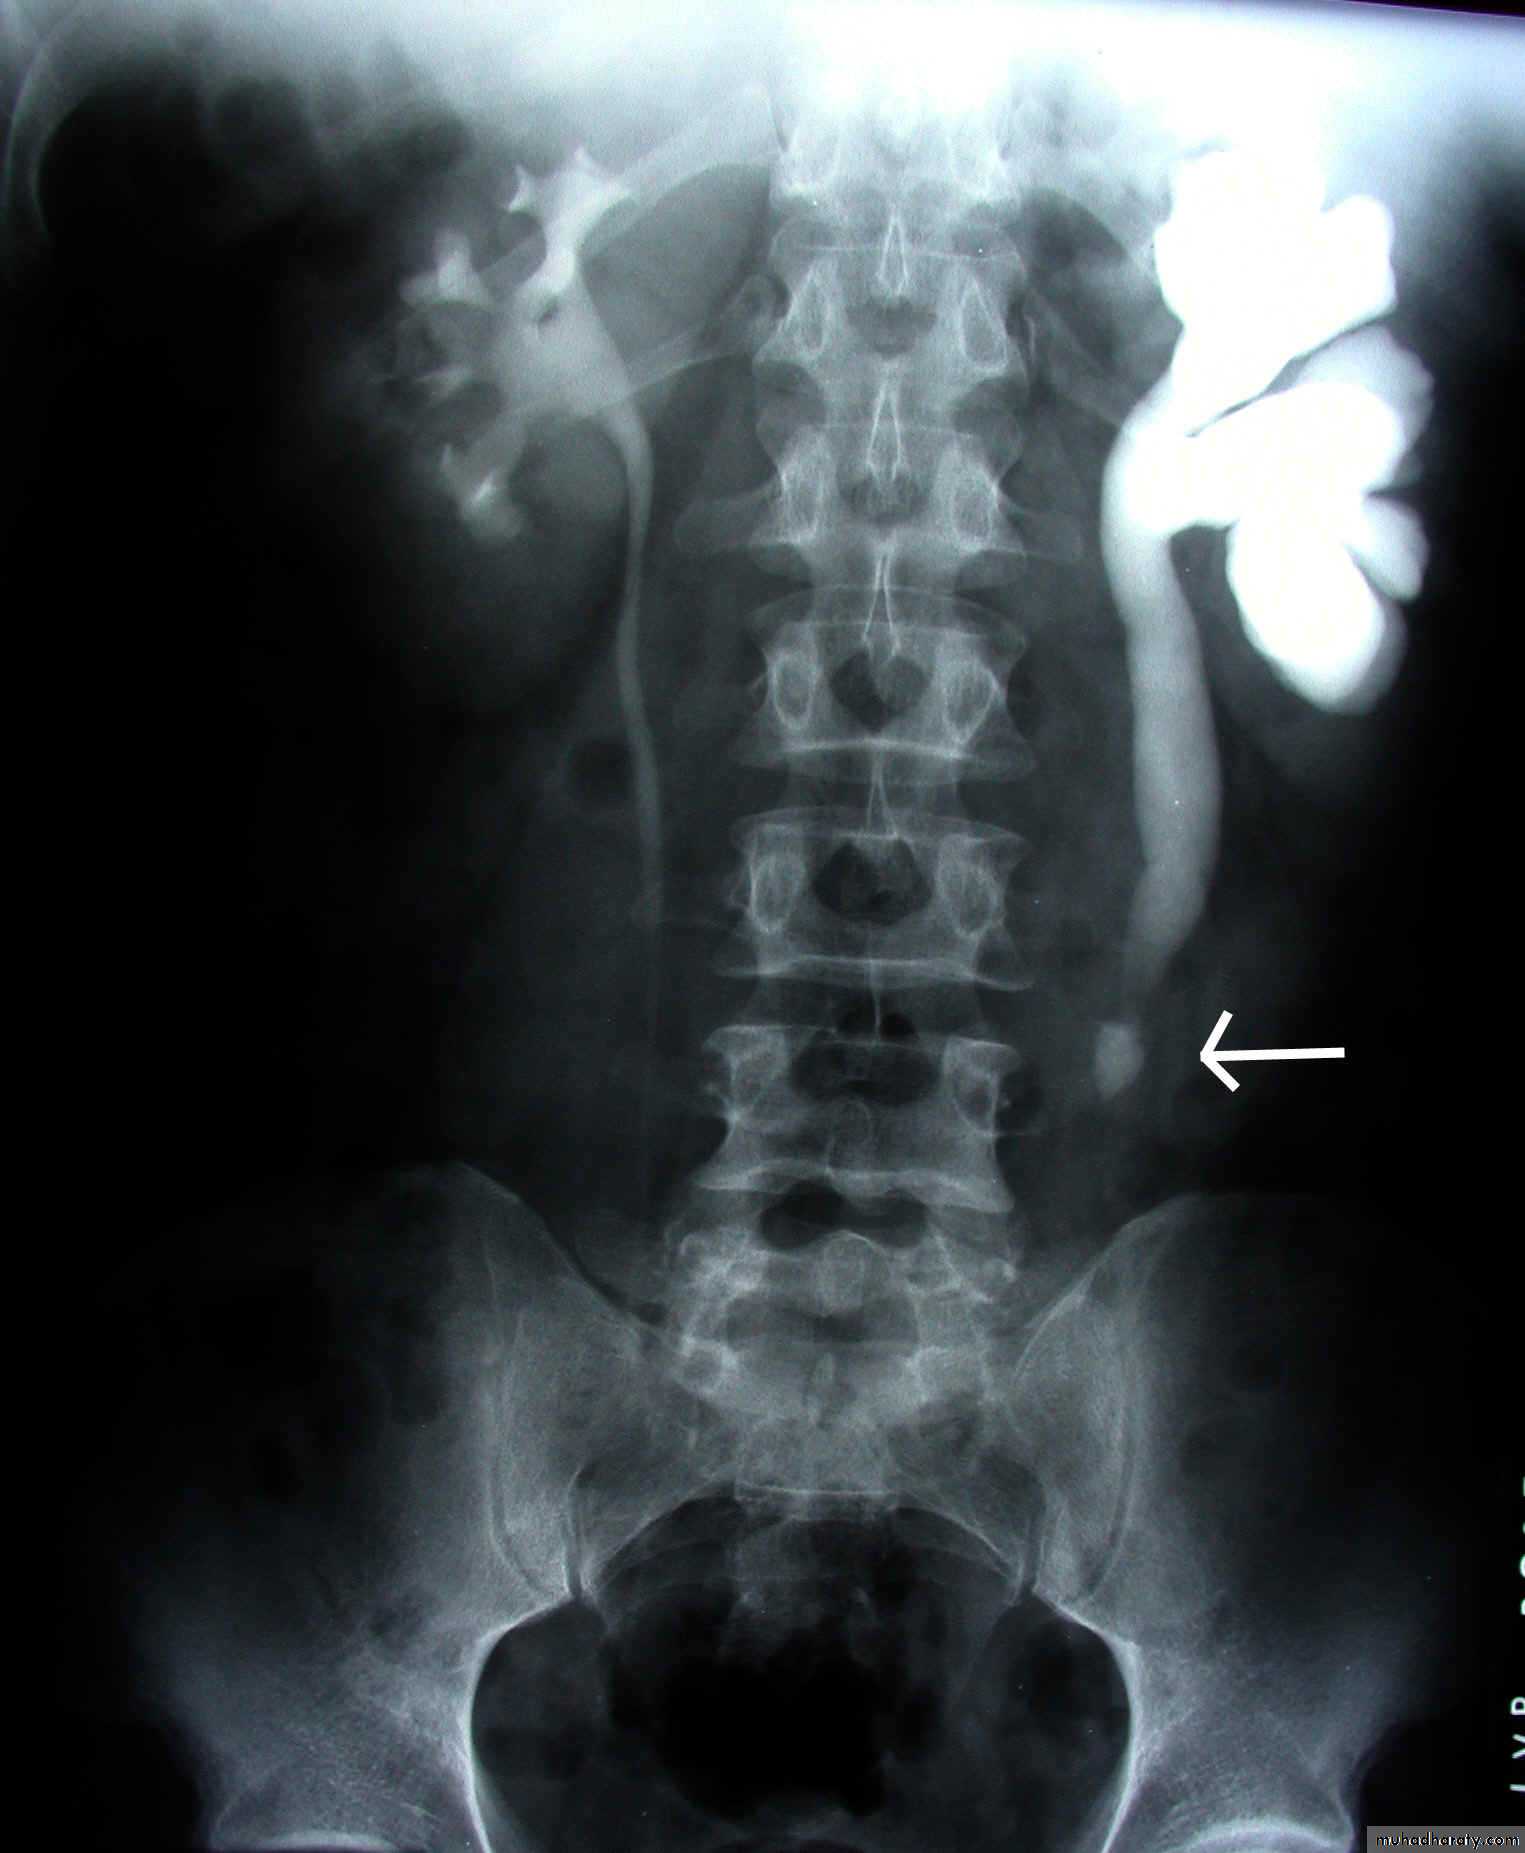

IVU excretory phase showing marked dilated PCS , but normal ureter …

DX congenital PUJ obstruction.Renal masses

IVU

Normal excretory phase of an IVU (intravenous urogram). This film was taken approximately 10 minutes following IV injection of iodinated contrast material. The kidneys are excreting contrast into non dilated calyces (arrows), renal pelvis (p), ureters (*) and bladder (B).